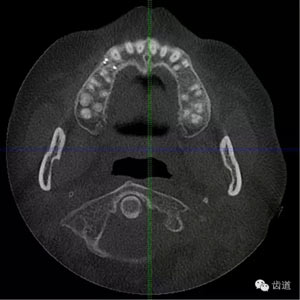

好的開始就是成功的一半。通過CBCT了解根管的位置,形態(tài),方向。

檢查顯示:近頰及腭根充填恰填,遠(yuǎn)頰根管內(nèi)有少許充填物影像。根尖明顯低密度影像。

處理:顯微根管治療。放置橡皮障,去除暫封,顯微鏡下超聲去除頰側(cè)根管上段部分牙本質(zhì),探及遠(yuǎn)中根管口,見有糊劑遮蓋。Path file根管疏通,M Two根管預(yù)備至2506#,配合3%次氯酸鈉和17%EDTA超聲蕩洗,干燥根管,放置氫氧化鈣糊劑,zoe暫封。

上頜第一前磨牙:87%為雙根管,其次為單根管,另有2.4%為三根管, 側(cè)支根管發(fā)生率49.5%;